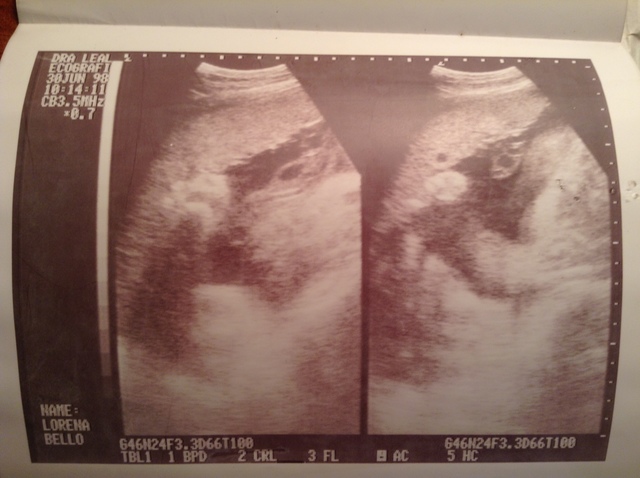

• ¡Ya viene en camino!

¡Ya viene en camino!

Fue la ecografía de seis meses de embarazo, donde a ella (mi madre) le contaron que venia un barón.